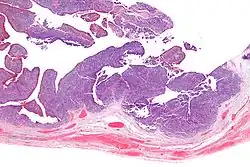

| Micrograph of transitional cell carcinoma of the ovary. H&E stain. |

Transitional cell carcinoma of the ovary (TCC of the ovary) is a rare type of ovarian cancer that has an appearance similar to urothelial carcinoma (also known as transitional cell carcinoma).[1]

TCC of the ovary is diagnosed by examination of the tissue by a pathologist. It has a characteristic appearance under the microscope and distinctive pattern of immunostaining.[2]

It is not related urothelial carcinoma.[1] It is in the transitional cell category of ovarian tumours which also includes malignant Brenner tumour and benign Brenner tumour.

Very high mag.